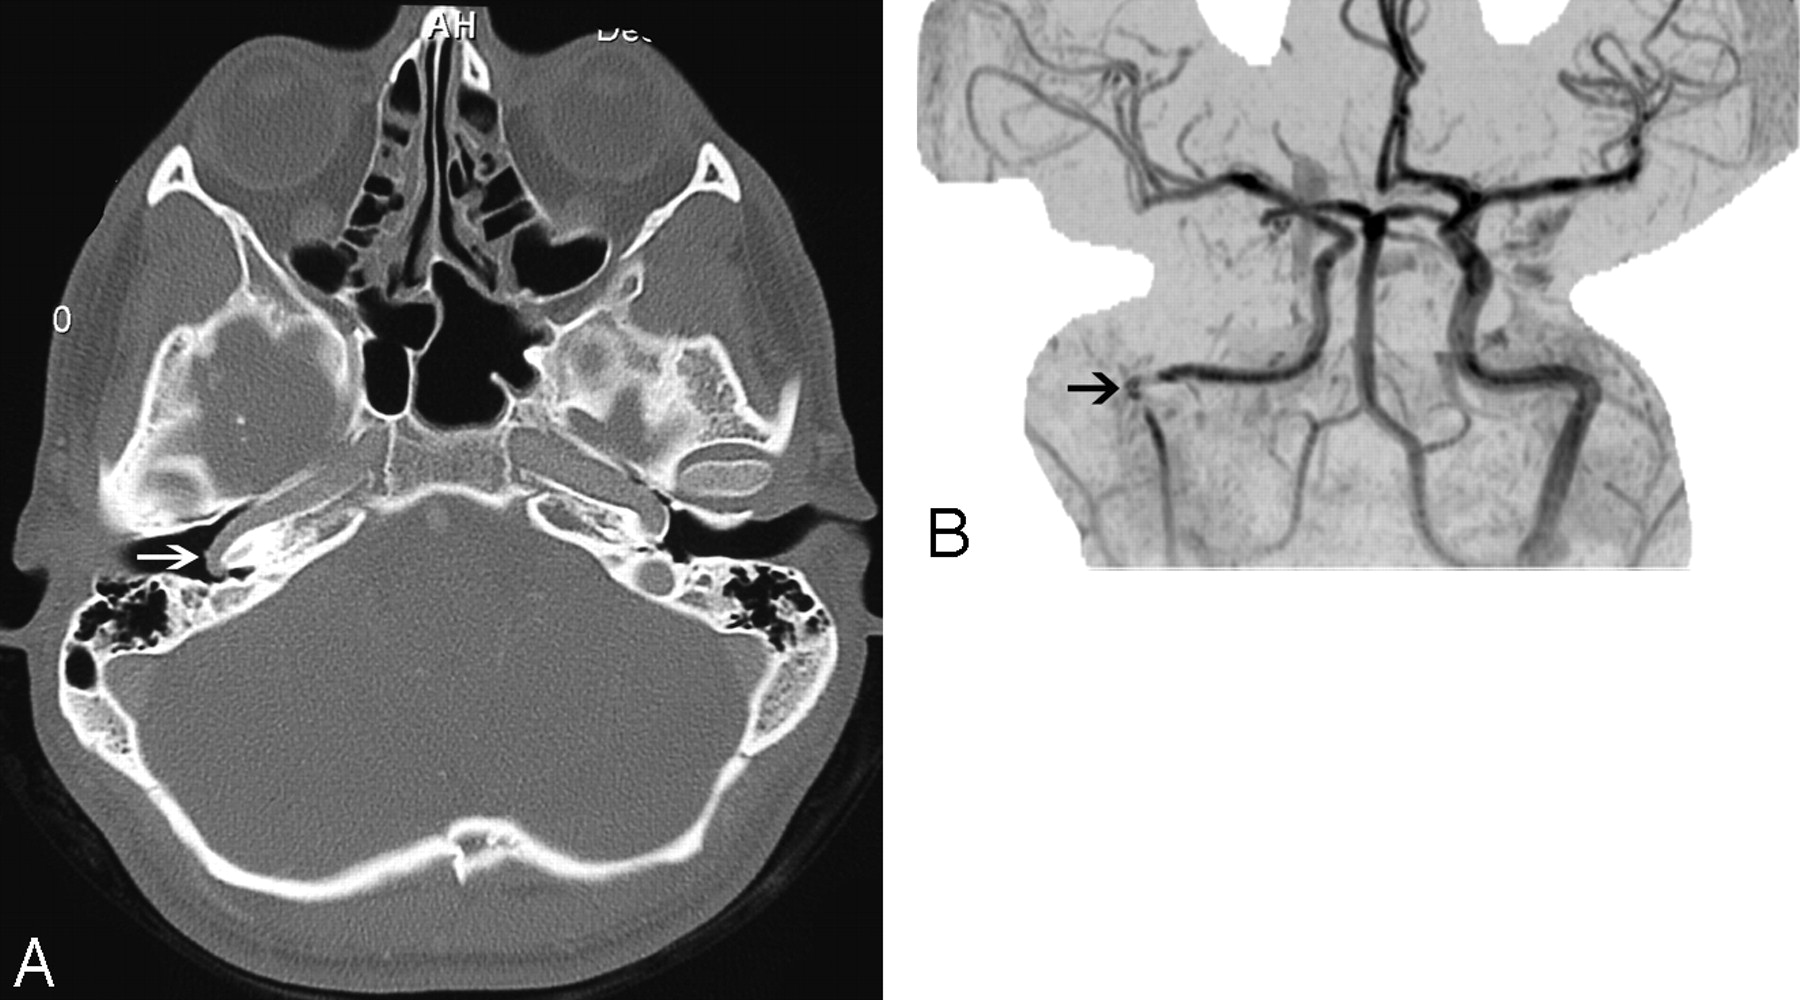

In early stages of otosclerosis, a radiolucent focus may be seen at the fissula ante fenestram, which is a cleft of fibrocartilaginous tissue located just anterior to the oval window. As the disease progresses, this lucency involves the margins of the oval and round windows and may even produce multiple radiolucent foci. Extension of the disease to the otic capsule may produce imaging signs of both fenestral and cochlear otosclerosis in the same patient. Cochlear otosclerosis is characterized by low-attenuation foci around the basal turn of the cochlea, though some lesions may also involve the lateral walls of the IAC and the cochlear promontory. In severe otosclerosis, a low-attenuation ring sometimes surrounds the cochlea, known as the double-ring sign. In the later healing phase, CT may show a “heaped-up” appearance along the margins of the oval and round windows and around the cochlea, indicating new bone formation (Figs 3 and 4). MR imaging is less sensitive for these findings, though T2-weighted images may show a high intraosseous signal intensity in the cochlear form of otosclerosis.6

Fenestral otospongiosis in a 35-year-old woman with hearing loss and tinnitus. Axial CT image demonstrates soft-tissue attenuation in the oval window (white arrow) and abnormal lucency at the fissula antefenestram (black arrow).

A 50-year-old man with cochlear otospongiosis. Axial CT scan demonstrates abnormal lucency surrounding the left cochlea (black arrows).